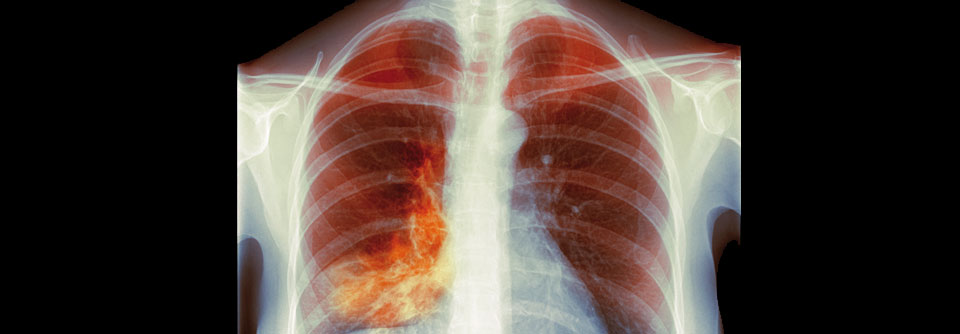

Bei Kindern, die schon früh eine Lungenentzündung haben, ist das Asthmarisiko deutlich erhöht. Bei Kindern, die schon früh eine Lungenentzündung haben, ist das Asthmarisiko deutlich erhöht. © nateejindakum – stock.adobe.com